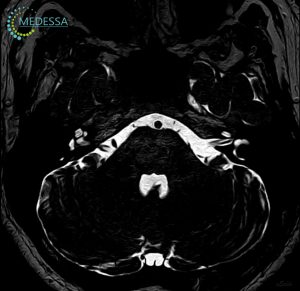

МРТ – найефективніший метод дослідження стану мозку. Він не лише безпечний і неінвазивний, а й надає детальну та точну інформацію, без впливу шкідливого опромінення, на відміну від рентгену чи КТ. МРТ голови дозволяє оцінити всі структури мозку, включаючи судини, мозкові оболонки та нервові корінці.

Цей метод дозволяє своєчасно виявляти різні захворювання, такі як пухлини, метастази, запальні процеси, дегенеративні зміни, деформації та інші патології, що дає змогу лікарям поставити точний діагноз і призначити ефективне лікування.

Для виявлення навіть незначних змін застосовуються 3D-послідовності та зрізи з високою роздільною здатністю.

Як результат, лікар отримує максимально точну інформацію про патології на ранніх стадіях, включаючи пухлини, за короткий час. Загальний час сканування голови без контрасту займає близько 10-15 хвилин.